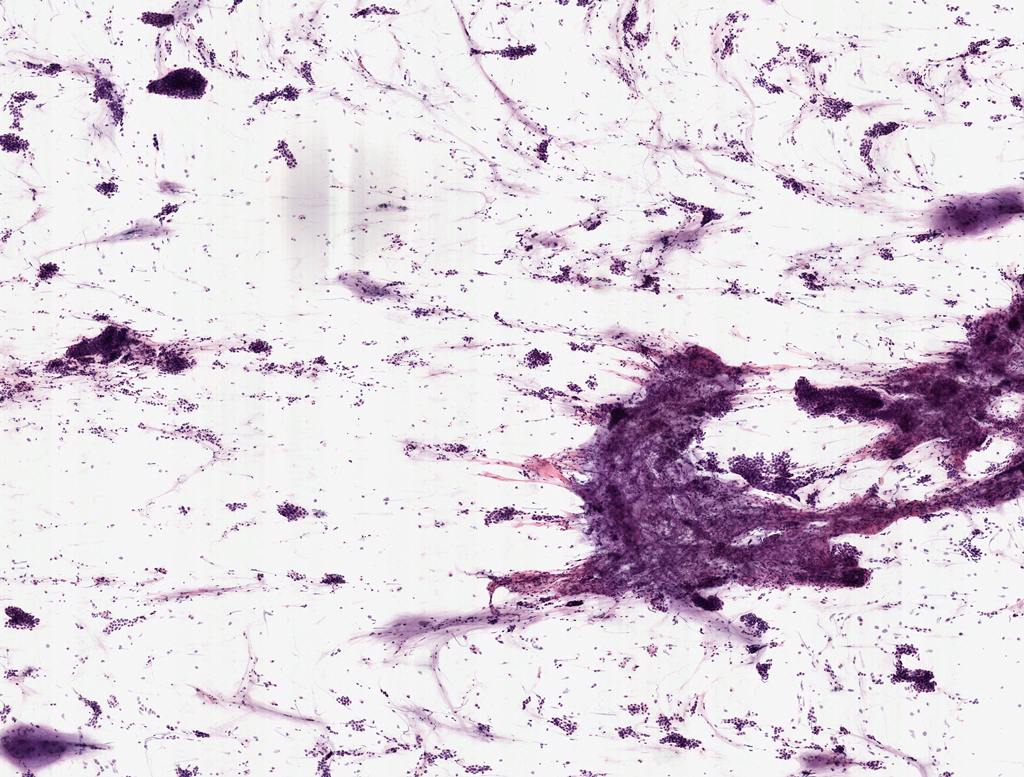

Áý´ãȸ¸í

Á¦Ãâ±â°ü

Organ

Sex

Age

712

Àü³²´ëÇб³º´¿ø

È丷¾×

M

64

111

711

ÇѾç´ë±¸¸®º´¿ø

Æó

F

42

92

710

°í´ë¾È¾Ïº´¿ø

33

83

709

¼­¿ï´ëÇб³º´¿ø

63

72

708

»ó°è¹éº´¿ø

71

78

707

Çѱ¹¿øÀÚ·ÂÀÇÇпø

41

79